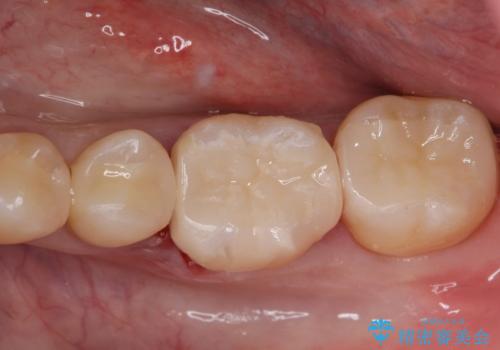

適合の良い詰め物が入りました。